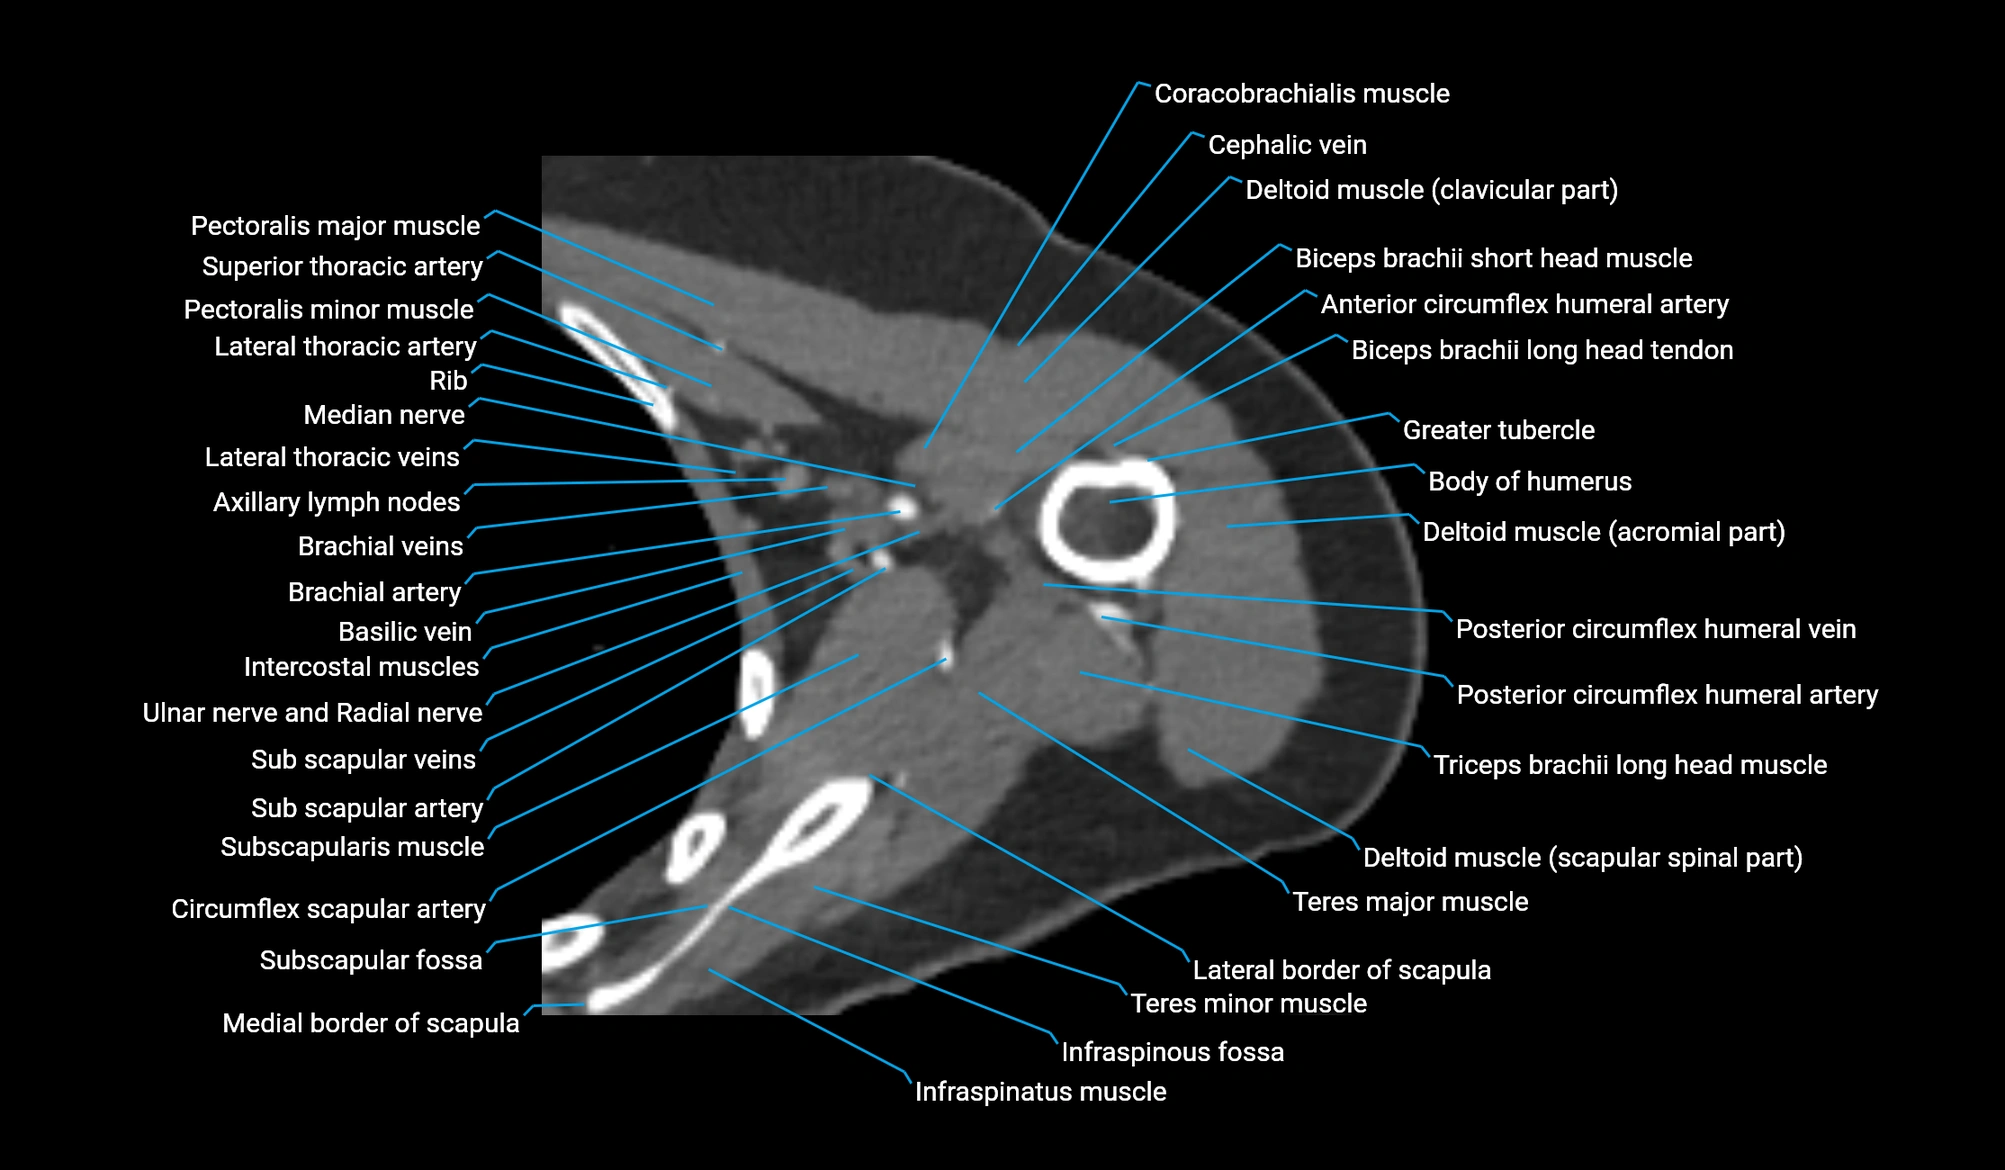

CT image